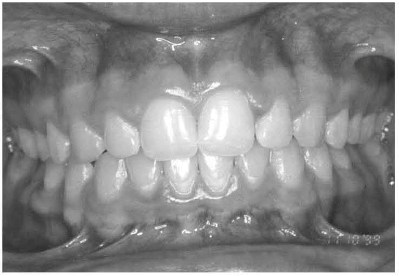

Below is an image of a typical occlusion.

Image 1. Typical Occlusion

So when we're looking at patients, we're looking at those beautiful smiles. This is what we would like to see. We would like to see the upper teeth covering the lower teeth by just a little bit, about one third of the tooth. We shouldn't see a lot of spaces in between the teeth either between two teeth that are side by side or top and bottom teeth. Any time we see extra spaces in teeth, that's a bit of a cause for concern and we try to figure out what else is going on there. But this is really what we would like to be seeing. Again, the below image is a normal occlusion - a beautiful smile that we would like to be seeing with these types of patients.